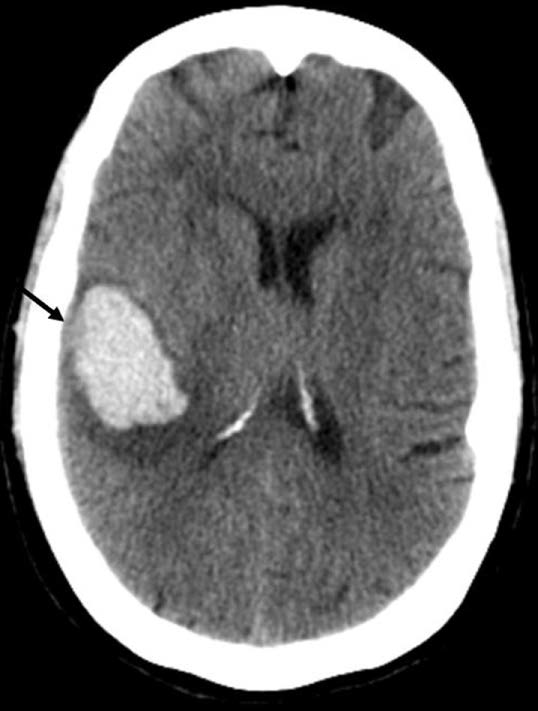

지난번 SAH에 이어 오늘은 ICH, 뇌내출혈에 대해서 알아보도록 하자.

CT and MRI

- CT와 MRI 모두 진단적으로 사용 가능하고, 검사방법에 따라 장단점이 존재한다.

- CT는 출혈의 범위, 뇌실내로 출혈이 확장되는지 확인하기 용이하다.

- MRI는 뇌의 구조적인 병변을 확인하는데 용이하다.

- 응급실에서는 검사의 접근성 문제로 non-contrast brain CT가 추천된다.

- 응급수술이 필요하지 않은 안정적인 환자일 경우엔 원인에 대한 정보를 얻기 위해 CT angiography를 추가로 시행한다.